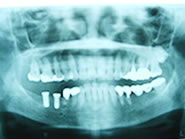

下顎右側の臼歯2本がありません

初診時のX線像です

2本のインプラントを埋入しました

手術後のX線像です